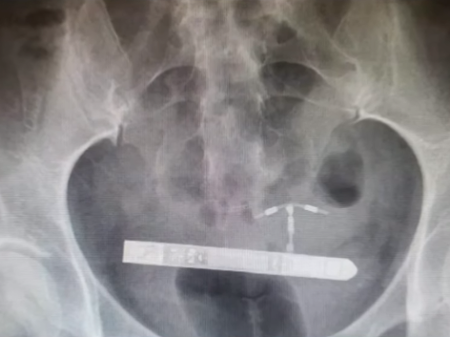

Mulher é submetida a cirurgia de emergência após vibrador parar na bexiga

EUA – | Uma norte-americana precisou ser submetida a uma cirurgia de emergência, depois que um vibrador ficou emperrado em sua bexiga.

Assim que chegou ao hospital, ela foi encaminhada para uma sala de emergência e fez diversos exames pélvicos para que os médicos se certificassem da localização exata do vibrador.

Os médicos determinaram então que o brinquedo sexual tinha penetrado no seu corpo através da uretra e se alojado ao lado da bexiga. Foi feita uma cirurgia para removê-lo e, após a recuperação, a mulher pretende entrar com uma ação contra a empresa.